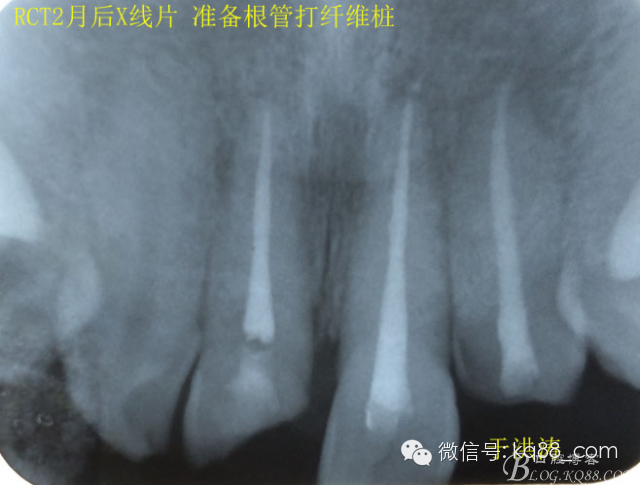

檢查:明顯可見22牙冠橫向斷裂至頸1/3處,近遠中與腭側斷裂至齦下??梢?/span>11牙冠斜向近中斷裂,近中與腭側均斷裂至齦下。21牙冠中1/3有裂痕。11 21 22松動(0),11 21叩(+),22叩(-),11 21 22探(-),11 21 22冷熱(-)。11 21 22唇側牙齦與粘膜和根尖相應部位未見明顯改變。11 22腭側牙齦增生性改變。11 21 22腭側粘膜和根尖相應部位未見改變。11 21 22舌側窩均有充填物。面部左右對稱無改變。余牙正常。(11,21,22牙冠顏色無改變)。 輔助檢查:X線片檢查11 22牙冠均有缺失。11 21 22 髓腔內均有充填物,11充填不到位, 21充填不實,22充填到位髓腔高密度影像。11 21 牙周膜有增寬,21根尖區(qū)有2mm左右低密度影像。未發(fā)現(xiàn)有牙根側穿或斷裂異物。 診斷:11,21慢性尖周炎,11,22殘冠。 治療計劃: 22無需治療。11 21 建議牙齒根管再治療。告知情況及費用。 1,11 21去除根充物。 2,11 21根管治療。 3,11 22纖維樁樹脂核修復。 4,高頻電刀去除11 22腭側牙齦組織到斷面。 5,11,21,22全瓷單冠修復牙齒。 治療過程:經(jīng)患者同意。H銼去除11 21原有充填物,未發(fā)現(xiàn)明顯滲出物,無異味。K銼疏通根管,VDW根測儀測量長度,11牙20mmWL,21牙20mmWL。S3鎳鈦器械預備根管。(全程1%次氯酸鈉沖洗EDTA溶解潤滑)試尖片顯示牙膠未到位,繼續(xù)向牙根尖各2mm進入預備。吸潮紙尖吸干根管,登士柏樹脂根充糊劑輸送至根尖部位,以測量數(shù)據(jù)用牙膠尖冷充側壓充填根管,3M玻璃離子封閉根管口。不可用患牙啃咬硬物,擇日冠修復。 輔助檢查:插針X線片顯示根管內充填物已經(jīng)取出。試尖片顯示牙膠尖未到位,繼續(xù)用K銼和機括向根尖預備。根充結束片顯示根充密實,無超充,無欠充。 醫(yī)囑:常規(guī)醫(yī)囑,不適隨診。 各步驟操作見下圖 于洪濤 2015.02.03 復 診 主訴:無疼痛,不適癥狀已經(jīng)消失。 檢查:11 21 充填物存在邊緣封閉完好,叩(-)松動(0)牙齦及周圍同初診。11 21 22無任何不適。 治療過程:由于患者自身原因即將兩個月來復診。拍X線片,去除11 22髓腔內部分牙膠,P鉆預備根管到達預定位置。粘結纖維樁,制作冠核。初預備11 21 22牙冠。高頻電刀按廠家要求功率和方法去除11 22腭側牙齦組織到達牙齒斷裂部位,調整檔位和功率繼續(xù)凝固和精修腭側組織,11 21 22排齦精修拋光。硅橡膠兩次法取模,可見模型完整肩臺清晰。制作臨時冠,科爾不含丁香油臨時冠粘結系統(tǒng)粘接。 模型送技師制作。預約義齒佩戴時間。(需術前牙齒比色) 輔助檢查:X線片顯示根尖低密度影像消失,牙周未見異常。X線片顯示纖維樁密合到位。 醫(yī)囑:不可用臨時牙肯咬硬物,不適隨診。 各步驟操作見下圖 于洪濤 2015.03.26 復 診 主訴:牙齒無癥狀,自感腭側術區(qū)舌舔粘膜不適。 檢查:臨時冠完整,無松動,邊緣緊密。牙齒無疼痛,唇側牙齦無明顯紅腫,腭側牙齦愈合良好,牙冠肩臺邊緣清晰。腭側牙齦術區(qū)中度觸及有少量滲血。 治療過程:義齒制作完成。去除臨時冠及粘結物。義齒試戴調整完全就位,無懸突,無縫隙。清洗義齒,氫氟酸處理義齒50秒(加強醫(yī)患防護),沖洗吹干,偶聯(lián)劑處理備用。基牙37%酸處理15秒,沖洗吹干,隔濕,排齦,涂第五代粘結劑。小蜜蜂雙固化樹脂水門汀激活攪拌注入義齒中,按順序就位,加壓力,牙線去除牙縫隙多余樹脂,涂阻氧劑,基牙唇腭側各光照固化3秒之后去除多余水門汀取出排齦線,繼續(xù)光照固化牙齒每個面20秒。精細查找去除多余水門汀。 醫(yī)囑:1,患牙咀嚼硬物加以注意。 2,常規(guī)醫(yī)囑,不適隨診,。 3,加強口腔衛(wèi)生意識。定期復診檢查。 各步驟操作見下圖 于洪濤 2015.04.07 回訪病例 主訴:咀嚼食物非常自如,無任何不適。 檢查:義齒牙體完整。無松動,無叩痛。唇側牙齦紅潤質韌無萎縮,腭側術區(qū)牙齦愈合良好,無炎癥改變。唇腭側根尖相應部組織無改變。余牙正常。 輔助檢查:X線片顯示牙根及周圍未見異常。未見骨萎縮。牙冠及頸部未見異常。 醫(yī)囑:定期檢查義齒,不適隨診。 各步驟操作見下圖 于洪濤2015.04.28